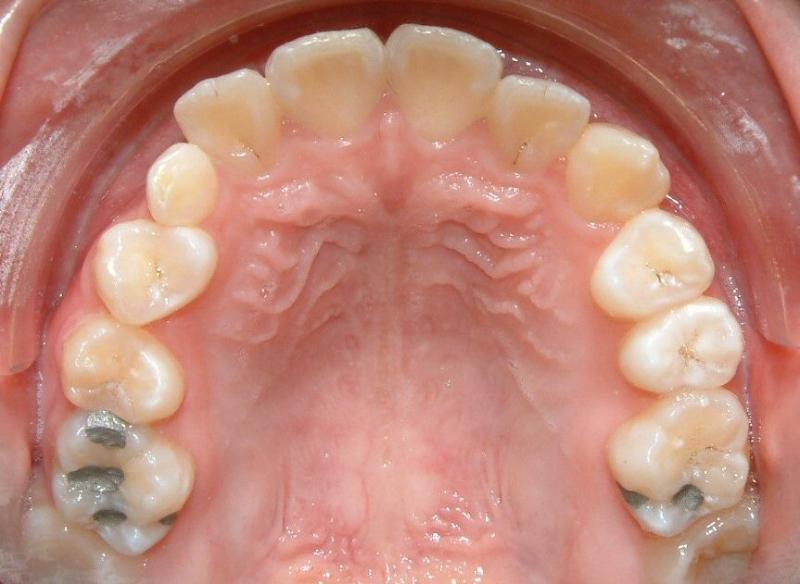

Without surgical exposure and forced eruption, there was practically very little progress with natural eruption of the upper right canine for nearly 3 years (not shown). With the surgical exposure (laser -> no bleeding) and forced eruption, the progress can be seen almost immediately - within a month (Fig. 9). After 2 months, the crown is more visible: part of the crown can be seen clearly (Fig. 10). After 8 months, the crown is moved into the position (Fig. 11). With additional 3 months, the crown is relatively well leveled and aligned (Fig. 12). It takes longer to treat the palatally impacted canine.

Fig. 12 Forced eruption, 11 months after surgical exposure (progress)

© Copyright 2007-2014, Vu Orthodontics. All rights reserved.